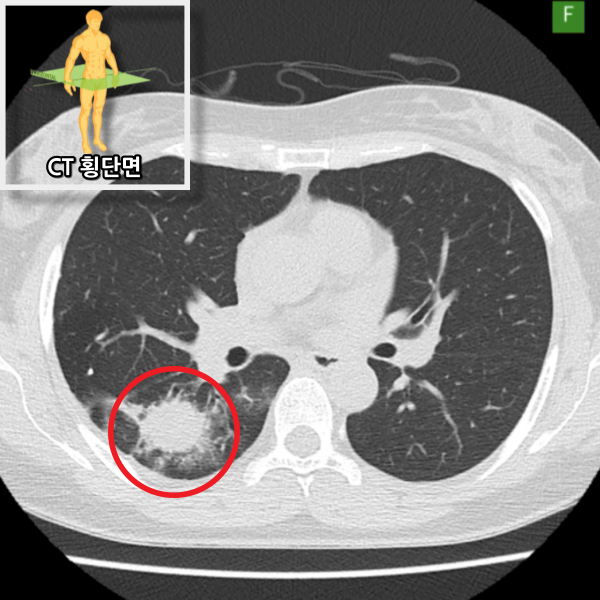

저선량 흉부 CT에서 우하엽에 염증성 고음영이 관찰되며 폐렴에 합당한 소견입니다. 이전 결핵을 앓은 적이 있어 추가 치료가 필요하다고 판단하여 상급병원으로 전원하였습니다.

• CT 횡단면 CT 횡단면